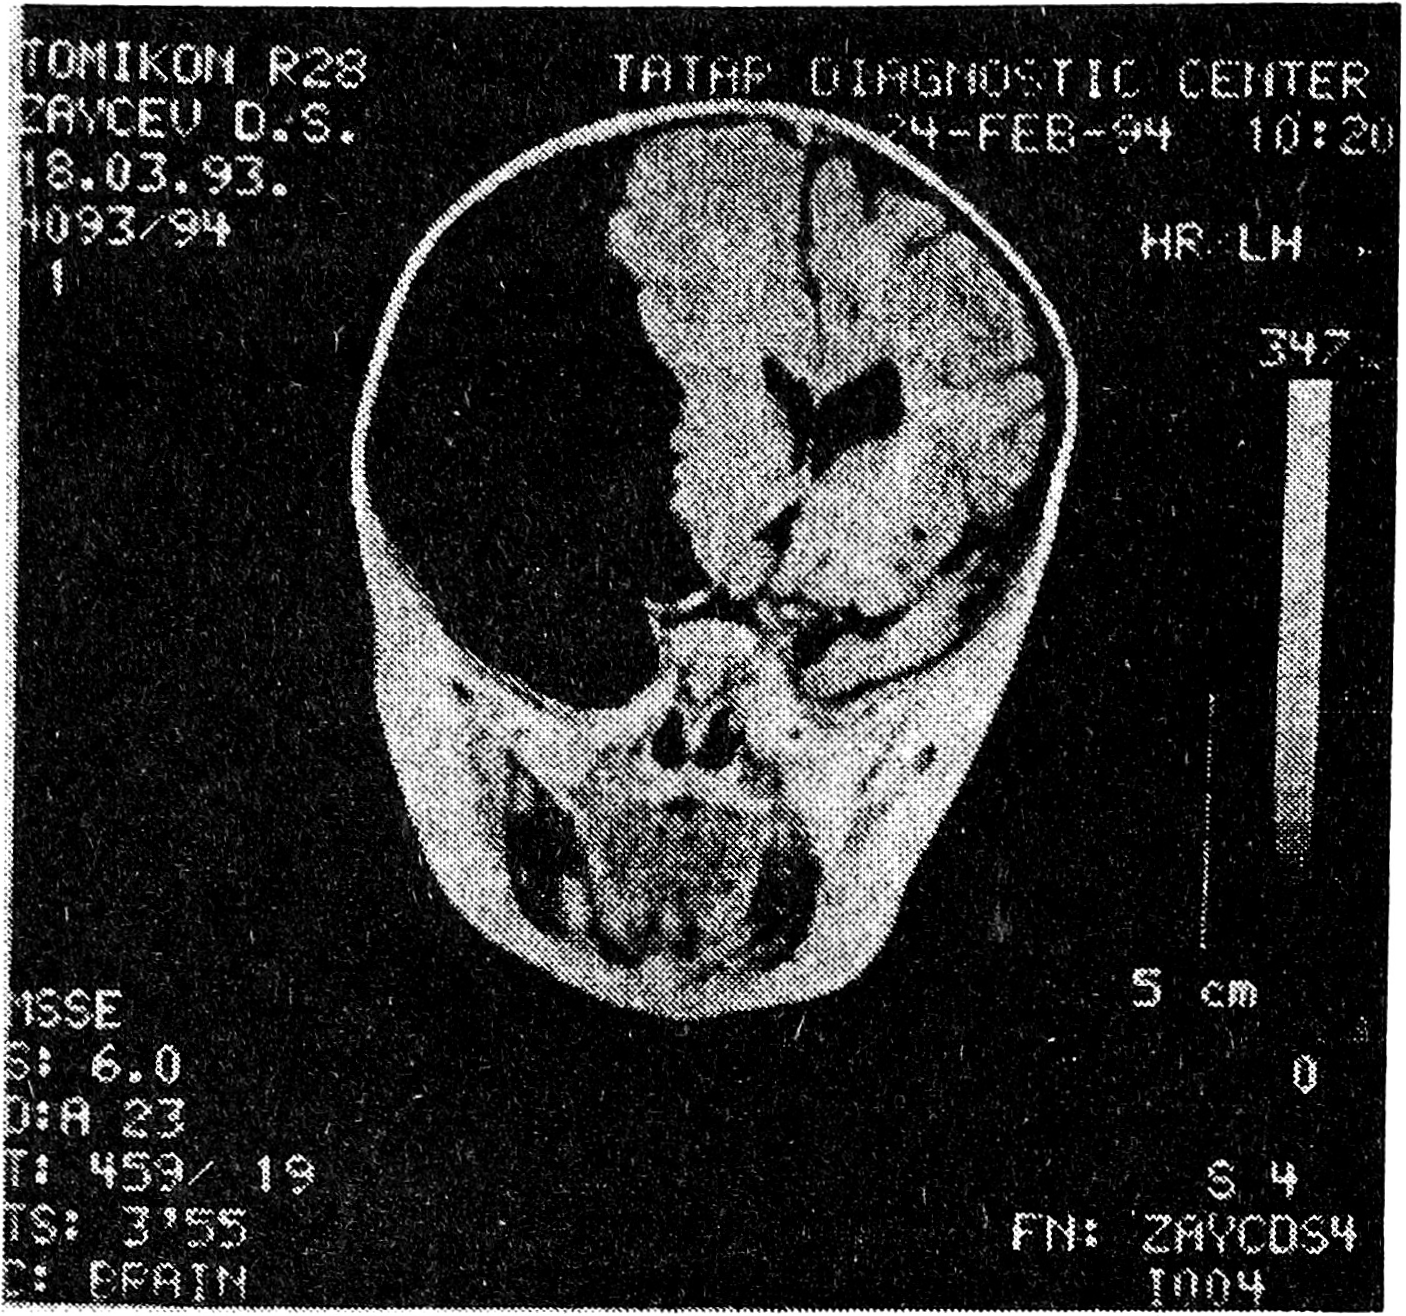

Рис. 3. ЯМР-томограмма арахноидальной кисты межполушарной щели головного мозга с анаплазией мозолистого тела.

Клинико-неврологическая диагностика ВАК крайне затруднительна. Большинство обследованных больных на втяжении длительного отрезка времени лечились по поводу вегетососудистых дисфункций, гипертензионно-гидроцефальных синдромов неясной этиологии, стойких остаточных явлений после перенесенных нейроинфекций, травматической энцефалопатии. Псевдотуморозный тип развития заболевания (прогредиентный или прогредиентно-ремиттирующий), сочетание гидроцефально-гипертензионного синдрома с медленно прогрессирующей или стабильно существующей очаговой симптоматикой на фоне краниографически верифицируемых гидроцефальных изменений в виде истончения кости, ее дуальных деформаций, углублений основания черепа настораживают в отношении возможности ВАК и определяют необходимость использования визуальных методов обследования мозга [3, 4]. Наиболее убедительные данные могут быть получены в результате выполнения ЯМР- и КТ-томографий, причем первый из упомянутых методов является наиболее информативным. Возможность получения ЯМР-томограмм практически в любой из желаемых плоскостей существенно расширяет разрешающую способность метода и позволяет с его помощью дифференцировать ВАК и кисты другой природы.